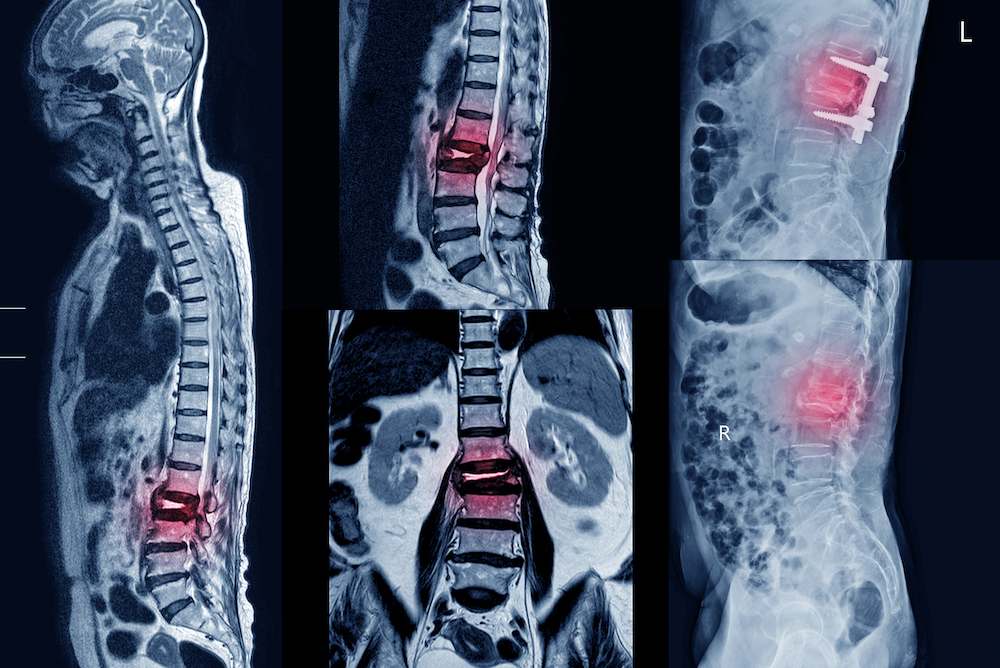

Что лучше — КТ или МРТ поясничного отдела позвоночника?

МРТ позвоночника - когда назначает врач, показания к проведению. Отличие от КТ.